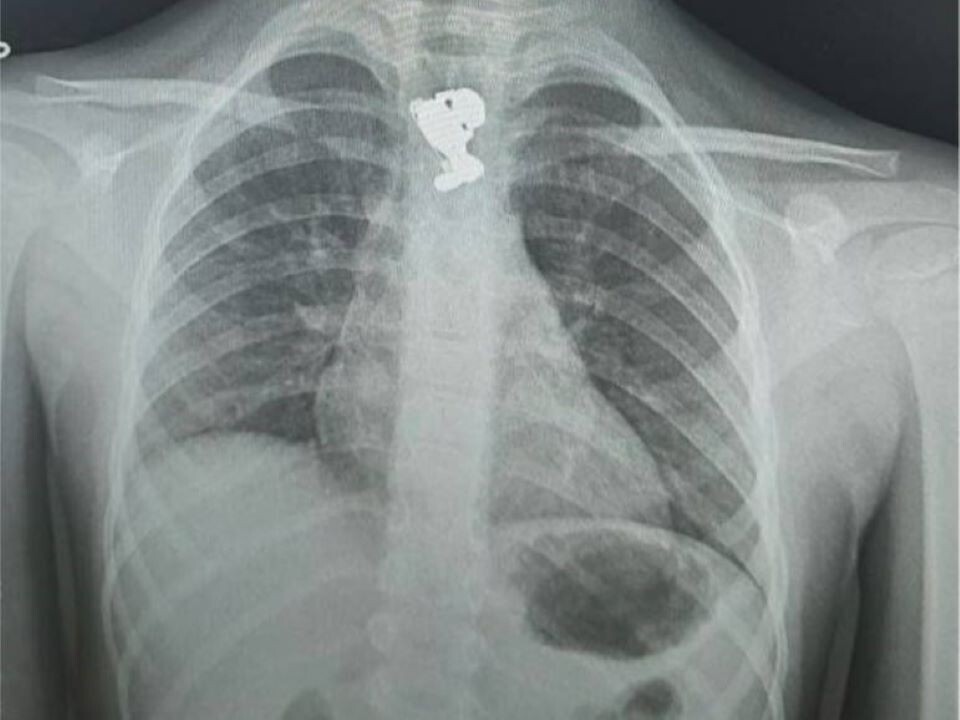

Фото: Министерство здравоохранения Московской области

Например, недавно в Подмосковье пятилетняя девочка была срочно доставлена в Детский клинический центр имени Л. М. Рошаля после того, как проглотила брошку в виде зайца. Врачи провели рентген, который подтвердил наличие инородного тела в пищеводе. Извлечение брошки оказалось непростым: при первой попытке она распалась на несколько частей. Врачам понадобилось использовать эндоскопические щипцы, чтобы достать булавку, а затем специальную корзину Дормиа для удаления самой броши.